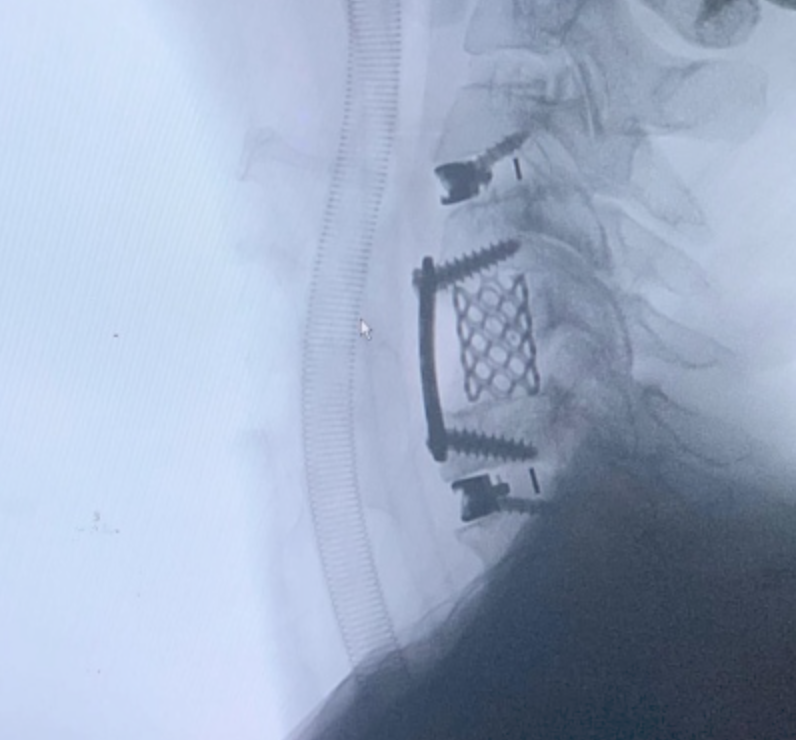

Cada procedimiento requiere una planificación detallada, basada en estudios de imagen y evaluación clínica, con el objetivo de lograr una descompresión adecuada de estructuras nerviosas y restaurar la estabilidad vertebral.

Se emplean técnicas quirúrgicas modernas, incluyendo abordajes mínimamente invasivos cuando son viables, lo que permite una recuperación más rápida y menor impacto en el paciente.

El enfoque está orientado a resultados funcionales, disminución del dolor y mejora significativa en la calidad de vida, siempre priorizando la seguridad y el bienestar del paciente.